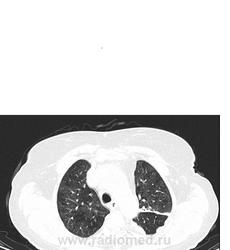

Мне видится хроническая ТЭЛА-упорно зрю мозаичность, видится сумасшедшая легочная гипертензия, застойные сердечные дела, и о ужас... мерещится мезотелиома... все эти узелки по плевре, каплевидны формы, прям по междолевочке... да и шарик в печени - али не гиповаскулярный метастаз???

ну неужели мои глюки и гипердиагностика??? не може же быть такое количество осумкованных плевритов???

ТЭЛА без контраста не исключишь. При таком гидротораксе добавил бы исследование на животе (или на боку, если ей это легче). Кстати, а почему сразу мезотелиома? А в легких застой и отек.

мезотелиома злокачественная сопровождается рецидивирующим большим гидротораксом, а доброкачественный вариант выглядит не так . Тут мне видится междолевой и костальный плеврофиброз , осумкавание жидкости по заднебоковой поверхности , возможно. На счет легких согласна с предыдущим мнением, хотя на счет отека у меня не повернулся бы язык.

В легких - мозаичный паттерн.

ЧТо это такое - это чередование повышенной(по типу матового стекла) и пониженой плотности в легочной ткани - неравномерные, неправильной формы (пятнистого - "patchy" характера).

Первое (и самое главное), что мы должны сделать когда видим такие изменения на КТ, это определиться - какие зоны при этом паттерне являются патологическими:

- патологическими являются зоны повышенной плотности (то есть мы видим участки уплотнения легочной ткани по типу "матового стекла" за счет частичного заполнения воздухоносных путей - жидкостью, клетками, фиброзом ) Зона пониженной пониженной плотности - это "нормальная" легочная паренхима.

- патологическими являются зоны пониженной плотности и обусловлены они нарушением перфузии указанных участков первичного или вторичного характера: первичного - при ТЭЛА (чаще всего ХТЛГ) - когда имеется обструкция сосудов и возникает первичная олтгемия, вторичного при обструктивных изменениях мелких бронхов и бронхиол - при этом просходит реактивное уменьшение и диаметра легочных сосудов (реактивня олигемия).

Во втором сучае (то есть если патологическими являются участки пониженной плотности)- мы имеем право обзывать этот паттерн - "мозаичной перфузией" - так как он обусловлен именно нарушеним перфузией.

- характер мозаичного паттерн. Для ХТЛГ больше характерна мозаичная перфузия с наличием сегментарных и субсегменатрных участков повышенной и пониженной плотности (как в этом случае)

В вышеприведенном случае - явных КТ-данных за наличие отек - я не вижу.

Вообщим на мой взгляд - ХТЛГ возможно рецидив.